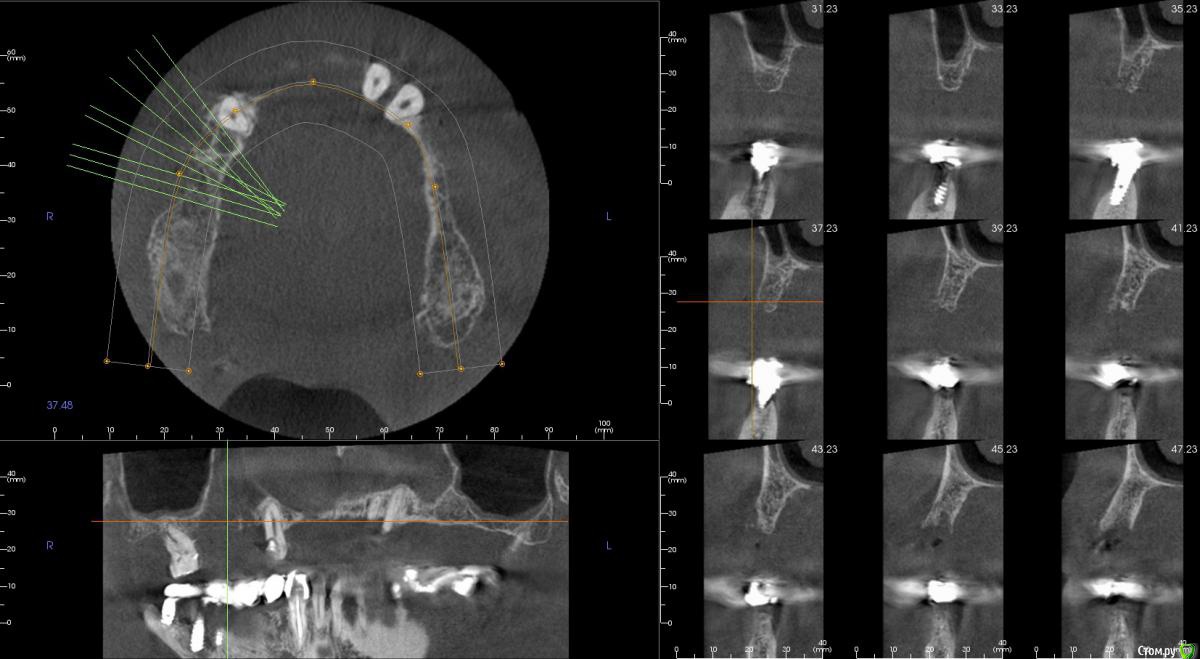

kamranchick Опубликовано 20 сентября, 2016 Поделиться Опубликовано 20 сентября, 2016 Интересует сторона 2. там хочу сделать соссидж, через несколько месяцев сделать закрытый синус и установить 2 винта в области 14 и 16, как вы думаете?и можно ли сделать конструкцию не брав во внимание фронтальный отдел? пациент финансово не тянет фронт Ссылка на комментарий

колесников Опубликовано 20 сентября, 2016 Поделиться Опубликовано 20 сентября, 2016 думаю не получится, так как придется аугментировать и фронтальный отдел и боковой отдел чтобы по хорошему сделать все на 4, тем более я работаю на Осстем, а у нас мультиков в системе нетНе нужно там ничего аугментировать. Меняете корни на импланты. В обл премоляров так же есть объём по снимку. Иначе череда костных и мягкотканных пластик с неясным прогнозом. Пациент точно не потянет. У остема платформа 4.0 совместима с астровской 4.5-5.0. Можно у астры взять запчасти. Ссылка на комментарий